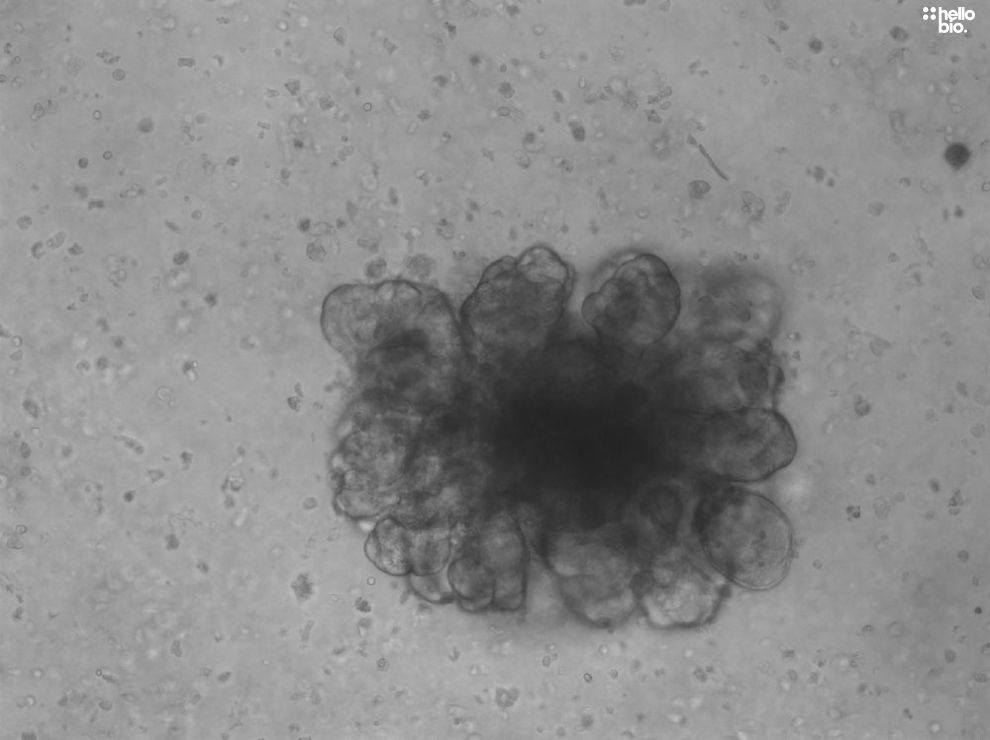

Figure. 1 Liver hepatocellular carcinoma tumouroids cultured with A83-01 (HB3218) and Forskolin (HB1348)

Liver hepatocellular carcinoma tumouroids cultured with A83-01 (HB3218) and Forskolin (HB1348)

Figures 1 - 3 show liver hepatocellular carcinoma tumouroids cultured with forskolin and A 83-01